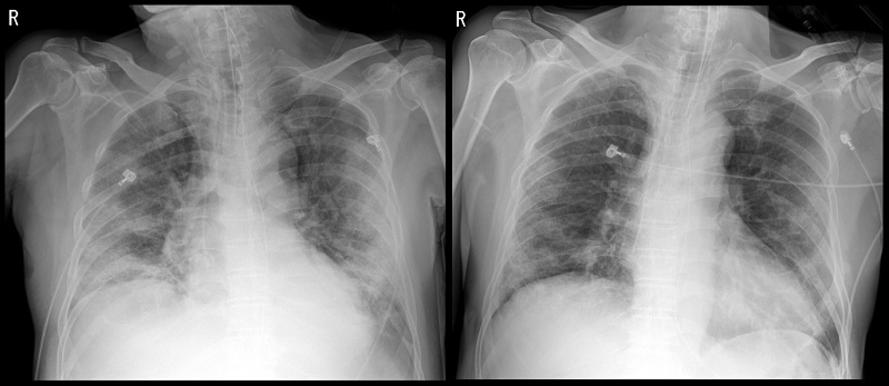

71세 남성 X-ray 사진<사진=세브란스병원>

김모(71, 남)씨는 열과 기침 증상을 보이다가 코로나19 확진을 받았다. 말라리아 치료제와 에이즈 치료제로 항바이러스 치료를 받았지만, 상태가 좋아지지 않아 세브란스병원으로 이송된 케이스다.

도착 당시 호흡 속도는 분당 30회 이상(정상 성인의 경우 20회 이하)으로 흉부 X-ray 검사에서도 양쪽 폐 모두 심각한 폐렴 증상을 보였다. 급성호흡곤란증후군으로 인공호흡기를 부착했지만, 상태는 좋아지지 않았다. 염증수치를 나타내는 C-반응성단백(CRP)의 경우 172.6mg/L(정상은 8mg/L 미만)까지 상승했다.

연구팀은 완치 판정을 받고 2주가 지난 남성의 회복기 혈장 500ml를 김씨에게 12시간 간격으로 두 번에 걸쳐 투여했고, 동시에 스테로이드 치료도 시작했다. 혈장치료와 스테로이드 치료를 받은 김씨의 경우 열이 떨어지고 CRP는 5.7mg/L로 정상범위로 떨어졌다.

흉부 X-ray 검사상 양쪽폐도 더 이상 나빠지지 않았다. 혈장을 투여받는 동안 특별한 부작용도 없었다. 현재 김씨는 인공호흡기를 제거했고, 코로나19 검사에서 음성 반응으로 완치 판정을 받았다.